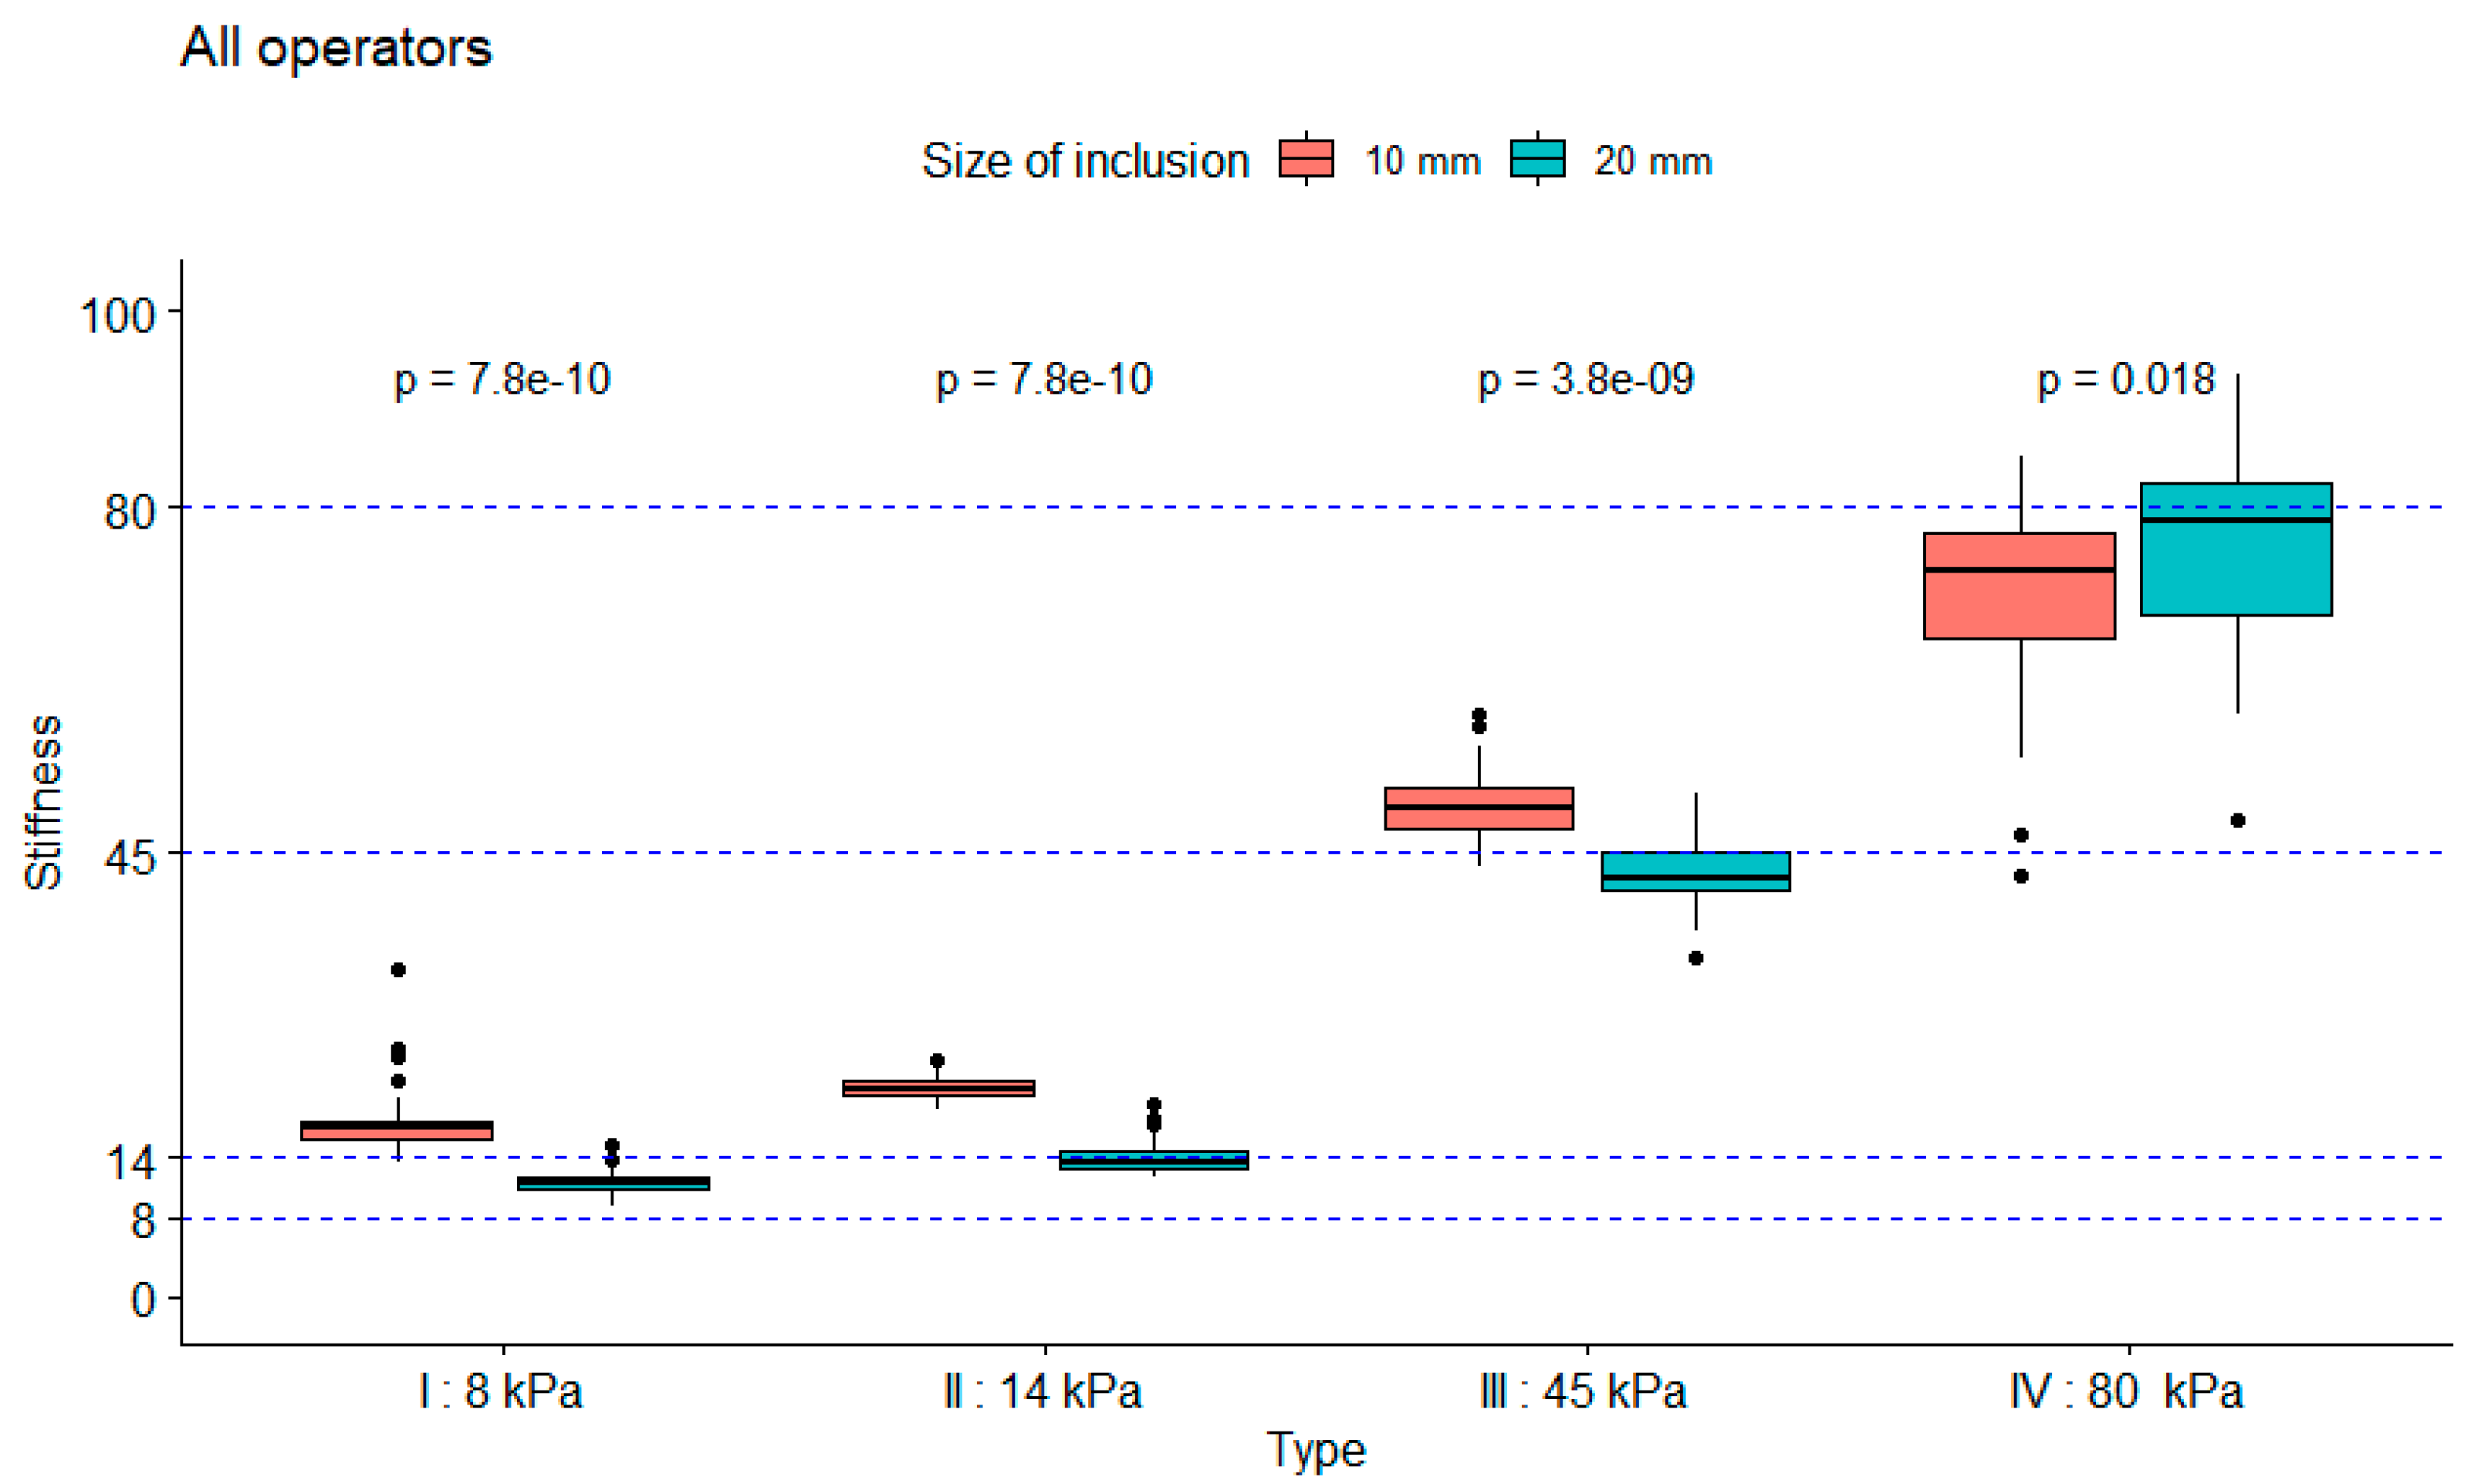

3.1. Robustness Evaluation Regarding Size and Type of Inclusions

3.2. Influence of Depth on Measured Stiffness